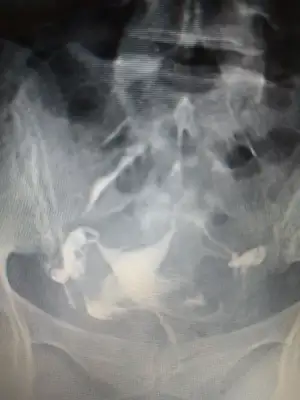

Onun hatlar karışık biraz. Çekim sonrası radyologun mesai saati bittiği için rapor yetişmemiş. Pazartesi alacak sonucunu. Kendi doktoru tüplerden birinde tıkanıklık var gibi konuşmuş ama başka doktorlara da göstermiş, basınçla açılmış demişler